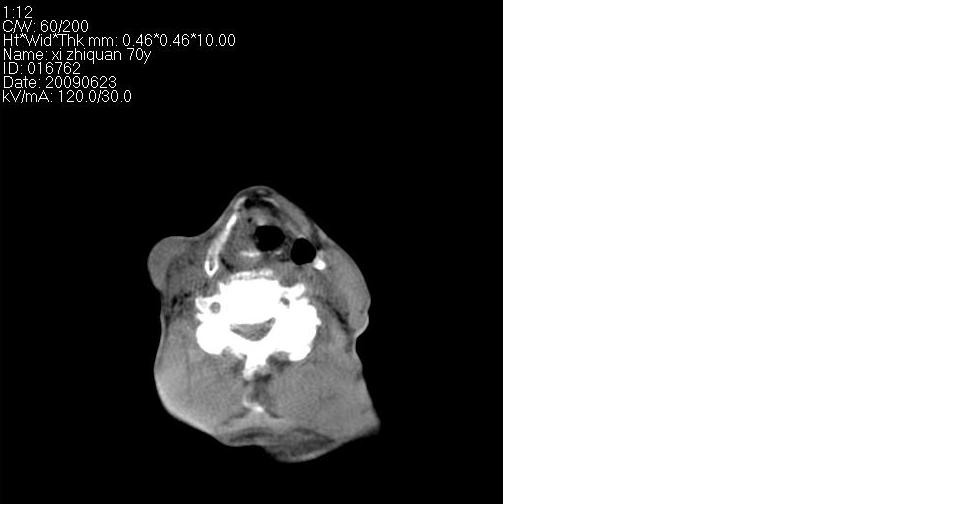

男 70岁,右侧颈部包块八个月余,下午及夜间疼痛加剧,包块质硬。化验穿刺镜下可见大量成堆裸核上皮细胞,可符合结核性淋巴结炎。

右侧颈部不规则软组织密度肿块影,密度均,边缘不清,颈筋膜间隙闭塞,向内致口喉咽受压变形,外达胸锁乳突肌深部,与之分界不清,周围骨质未见异常。